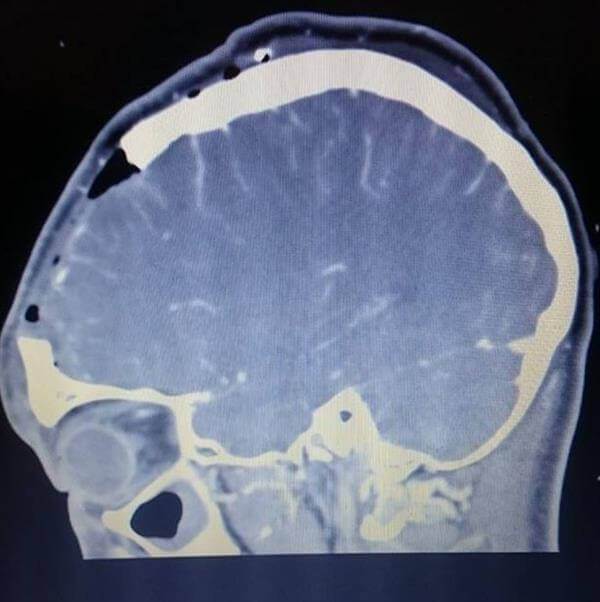

Die Ärzte im John Radcliffe Hospital in Oxford diagnostizierten ein Psammomatös Juvenile Ossifying Fibroma, ein gutartiger, aber seltener Tumor. In ihrem letzten Highschool Jahr unterzog sich Tiffany der Operation, um den Tumor zu entfernen. Sechs Stunden benötigten die Ärzte, den Tumor durch ihre Nase zu ziehen. Ein paar Tage nach der Operation war klar, dass etwas nicht stimmte, da Tiffany noch nicht wieder reagierte. Ihr Gehirn war stark angeschwollen und drückte gegen die Schädeldecke. Die Ärzte sahen sich gezwungen ein Stück des Schädels zu entfernen.

Trotz des fehlenden Stücks in ihrem Kopf, konnte Tiffany in ihr normales Leben zurückkehren, machte ihre Abschlussprüfungen und ging ihrem Nebenjob nach. Die Ärzte sagten Tiffany, dass ihr Stück Schädel von einem 3D-Drucker hergestellt wird. Das Dauerte jedoch über 3 Wochen, da es eine Verzögerung in der Firma gab. Das Schädelimplantat wurde nach CT- und MRT-Scans ihres Kopfes gefertigt. Nachdem die Ärzte sicher sein konnten, dass ihr Hirn nicht mehr anschwellen wird, setzten sie das Implantat aus Kalzium, Kunststoff und Titan ein.